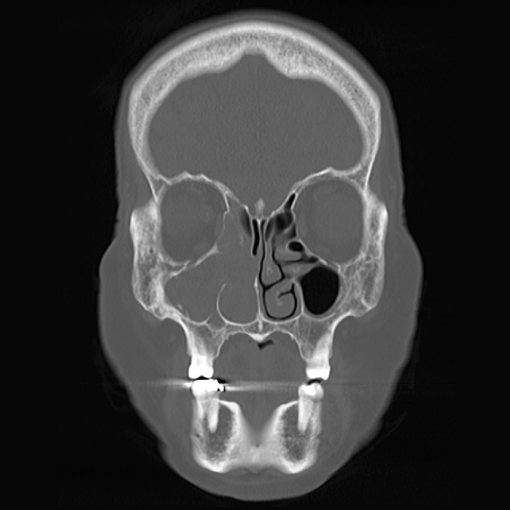

より正確な診断と適切な治療のため、モリタ社製コンビームCTを導入しています。

超高解像度で詳細な構造まで確認できるのは勿論、

一般的なCT(ヘリカルCT)に比べて1/7以下の被曝量に抑えることができます。

副鼻腔炎や鼻骨骨折、特殊な中耳炎の診断や重症度の判定を行うことができます。